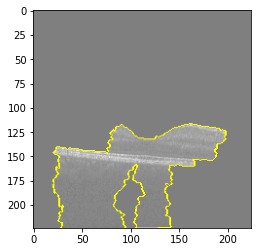

Explanation B

Explanation B

Explanation B

Explanation B

Fig 6, 7, 8 and 9 depicts the visualization of correct predictions by our proposed CNN model where fig 6 is class CNV, fig 8 is class DME, fig 7 is DRUSEN and finally, fig 9 is NORMAL. Here the first photo in every class is the original image. The LIME map of our suggested model’s prediction is shown in image B whereas in image C the positive region is highlighted in specific sections on the original image. For Image D we have increased the number of features from 5 to 10 thus more regions have been predicted as the positive region which is highlighted in green. After increasing the features from 5 to 10, some of the regions are predicted wrongly. The red regions represent the output of incorrect prediction. The following image represents the Grad-CAM heatmap highlighting the regions with our model’s prediction.